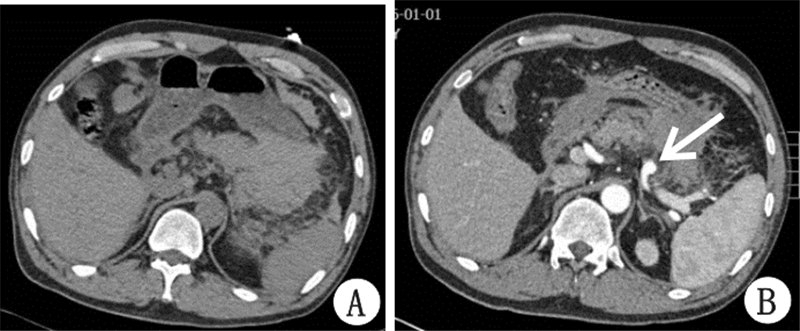

患者男,46岁,因“腹部持续性胀痛6 h”急诊入院。入院前6 h患者无明显诱因出现持续性全腹胀痛。否认外伤史。既往史:10年前患急性胰腺炎,10年来胰腺炎反复发作。查体:神志清楚,心率90次/min,血压122/65 mmHg(1 mmHg=0.133 kPa),全腹压痛,以脐周及左上腹明显,伴肌紧张,无反跳痛。门诊检Hb 111 g/L,腹部CT(图 1A):①胰腺形态欠光整,胰尾部略饱满,密度欠均匀。脾血管密度欠均匀。②肝周少量积液,脾周、腹腔及网膜囊积血、积液。腹腔穿刺抽出不凝血。怀疑腹腔脏器自发性或隐匿型破裂。入院后患者心率、血压正常,Hb稳定,行全腹CT三期增强(图 1B)提示:①脾动脉瘤,最大直径约1 cm。②腹腔及网膜囊积血较前次无明显变化。初步判断腹腔脏器自发性或隐匿型破裂,脾动脉瘤破裂可能性不大,但考虑患者仍有近期或远期再次发生腹腔活动性出血而危及生命的风险,建议尽早手术治疗出血灶及脾动脉瘤,但患者要求保守、观察治疗。入院后第2天清晨,患者突发剧烈腹痛。查体:患者烦躁,面色苍白,心率136次/min,血压83/52 mmHg;全腹压痛、反跳痛及肌紧张,以左上腹为著。急检Hb 67g/L。考虑患者发生严重腹腔内出血,立即抗休克治疗同时紧急行剖腹探查术。入手术室血压60/30 mmHg,术中见腹腔大量新鲜血及黑褐色陈旧性血块,量约3000 mL,脾动脉瘤破裂出血,脾上极一长约1.5 cm、深约2.0 cm裂口,胰尾部与周围组织粘连重。术中诊断:脾动脉瘤破裂、自发性脾破裂。行脾动脉结扎止血、脾切除术。术后病理回报:脾被膜下灶状出血,证实术中诊断。患者术后治疗好转出院。

| A:平扫;B:三期增强动脉期(箭头示脾动脉瘤) 图 1 患者腹部CT结果 |